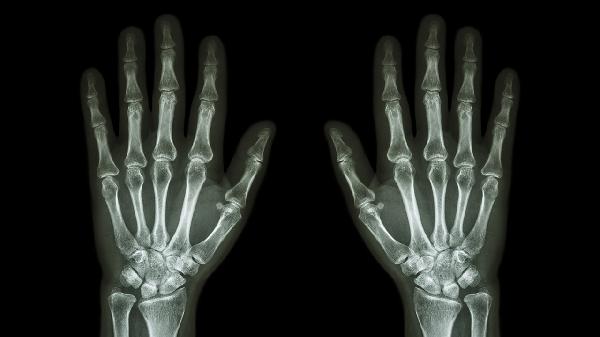

关节扭伤、骨折或脱位可直接导致拇指关节畸形和疼痛。需通过X线或MRI明确损伤程度,轻微损伤可制动冷敷,骨折需石膏固定,严重韧带断裂可能需关节镜手术修复。恢复期可配合红外线理疗促进愈合。